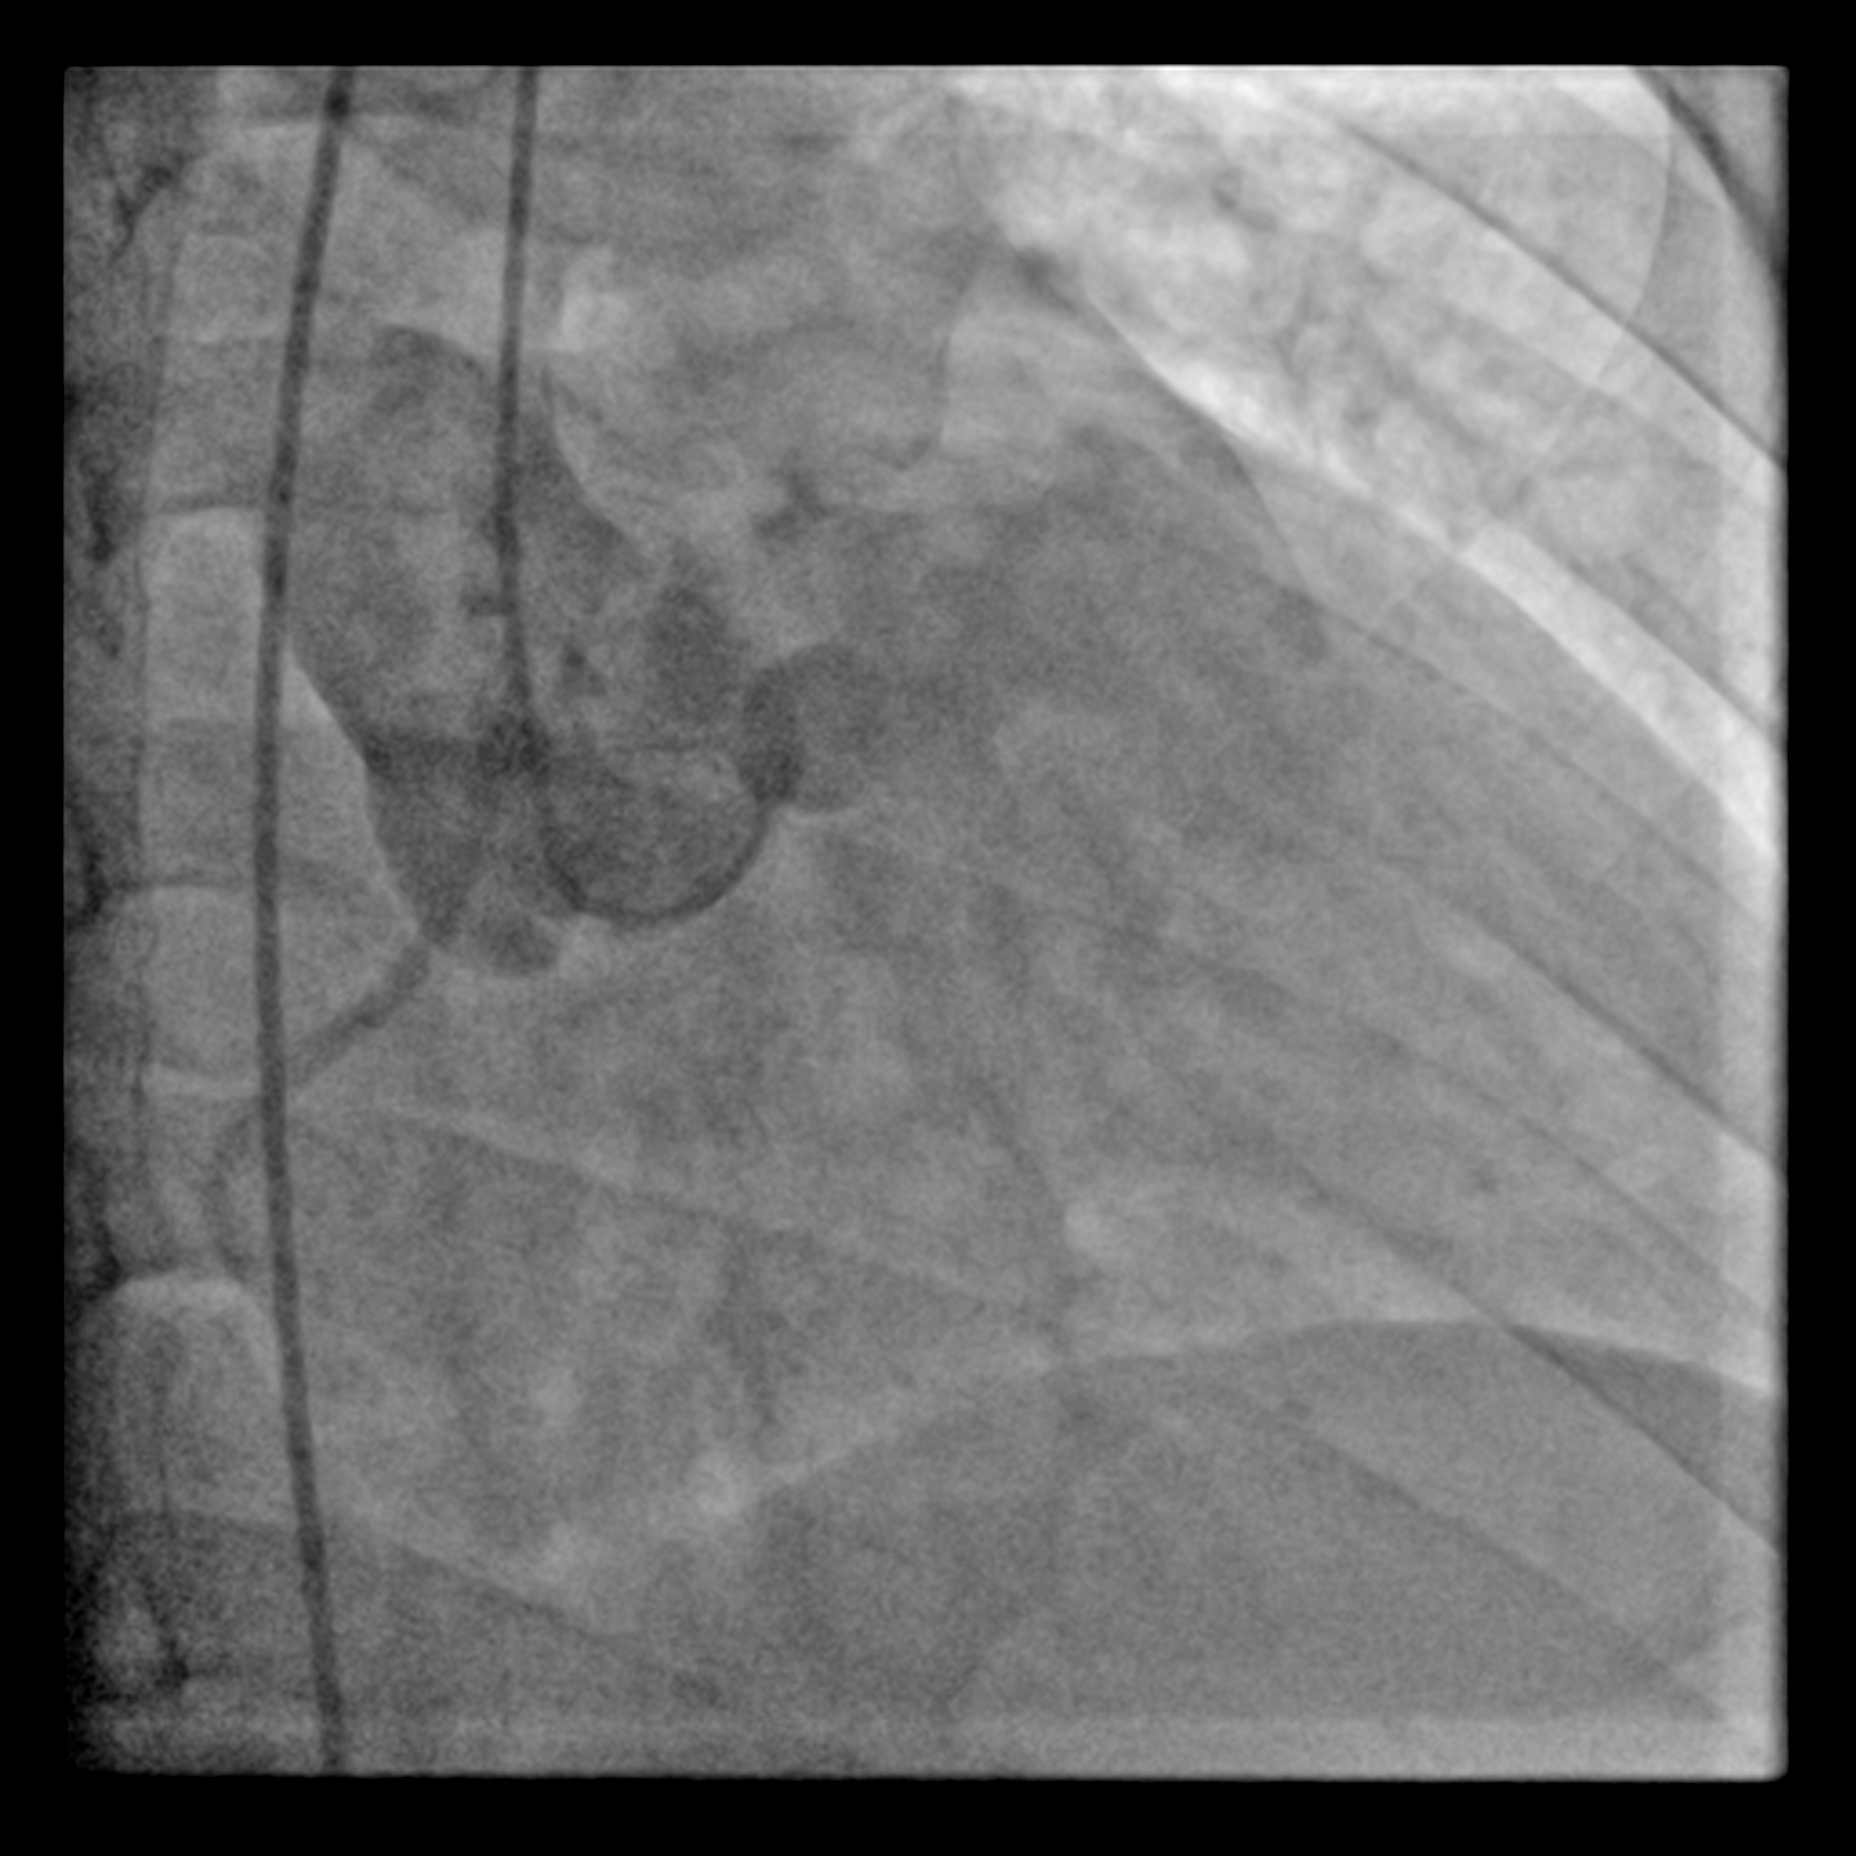

Via right femoral arterial access, a pigtail catheter was placed in SOV & non selective shot was taken with injector 2 views were used: left anterior and right anterior oblique view were taken to delineate the shunt. Right heart catheterisation was not perform in view of absence of pulmonary hypertension albeit left ventricle is dilated from echocardiography.

LAO.mp4

RAO.mp4